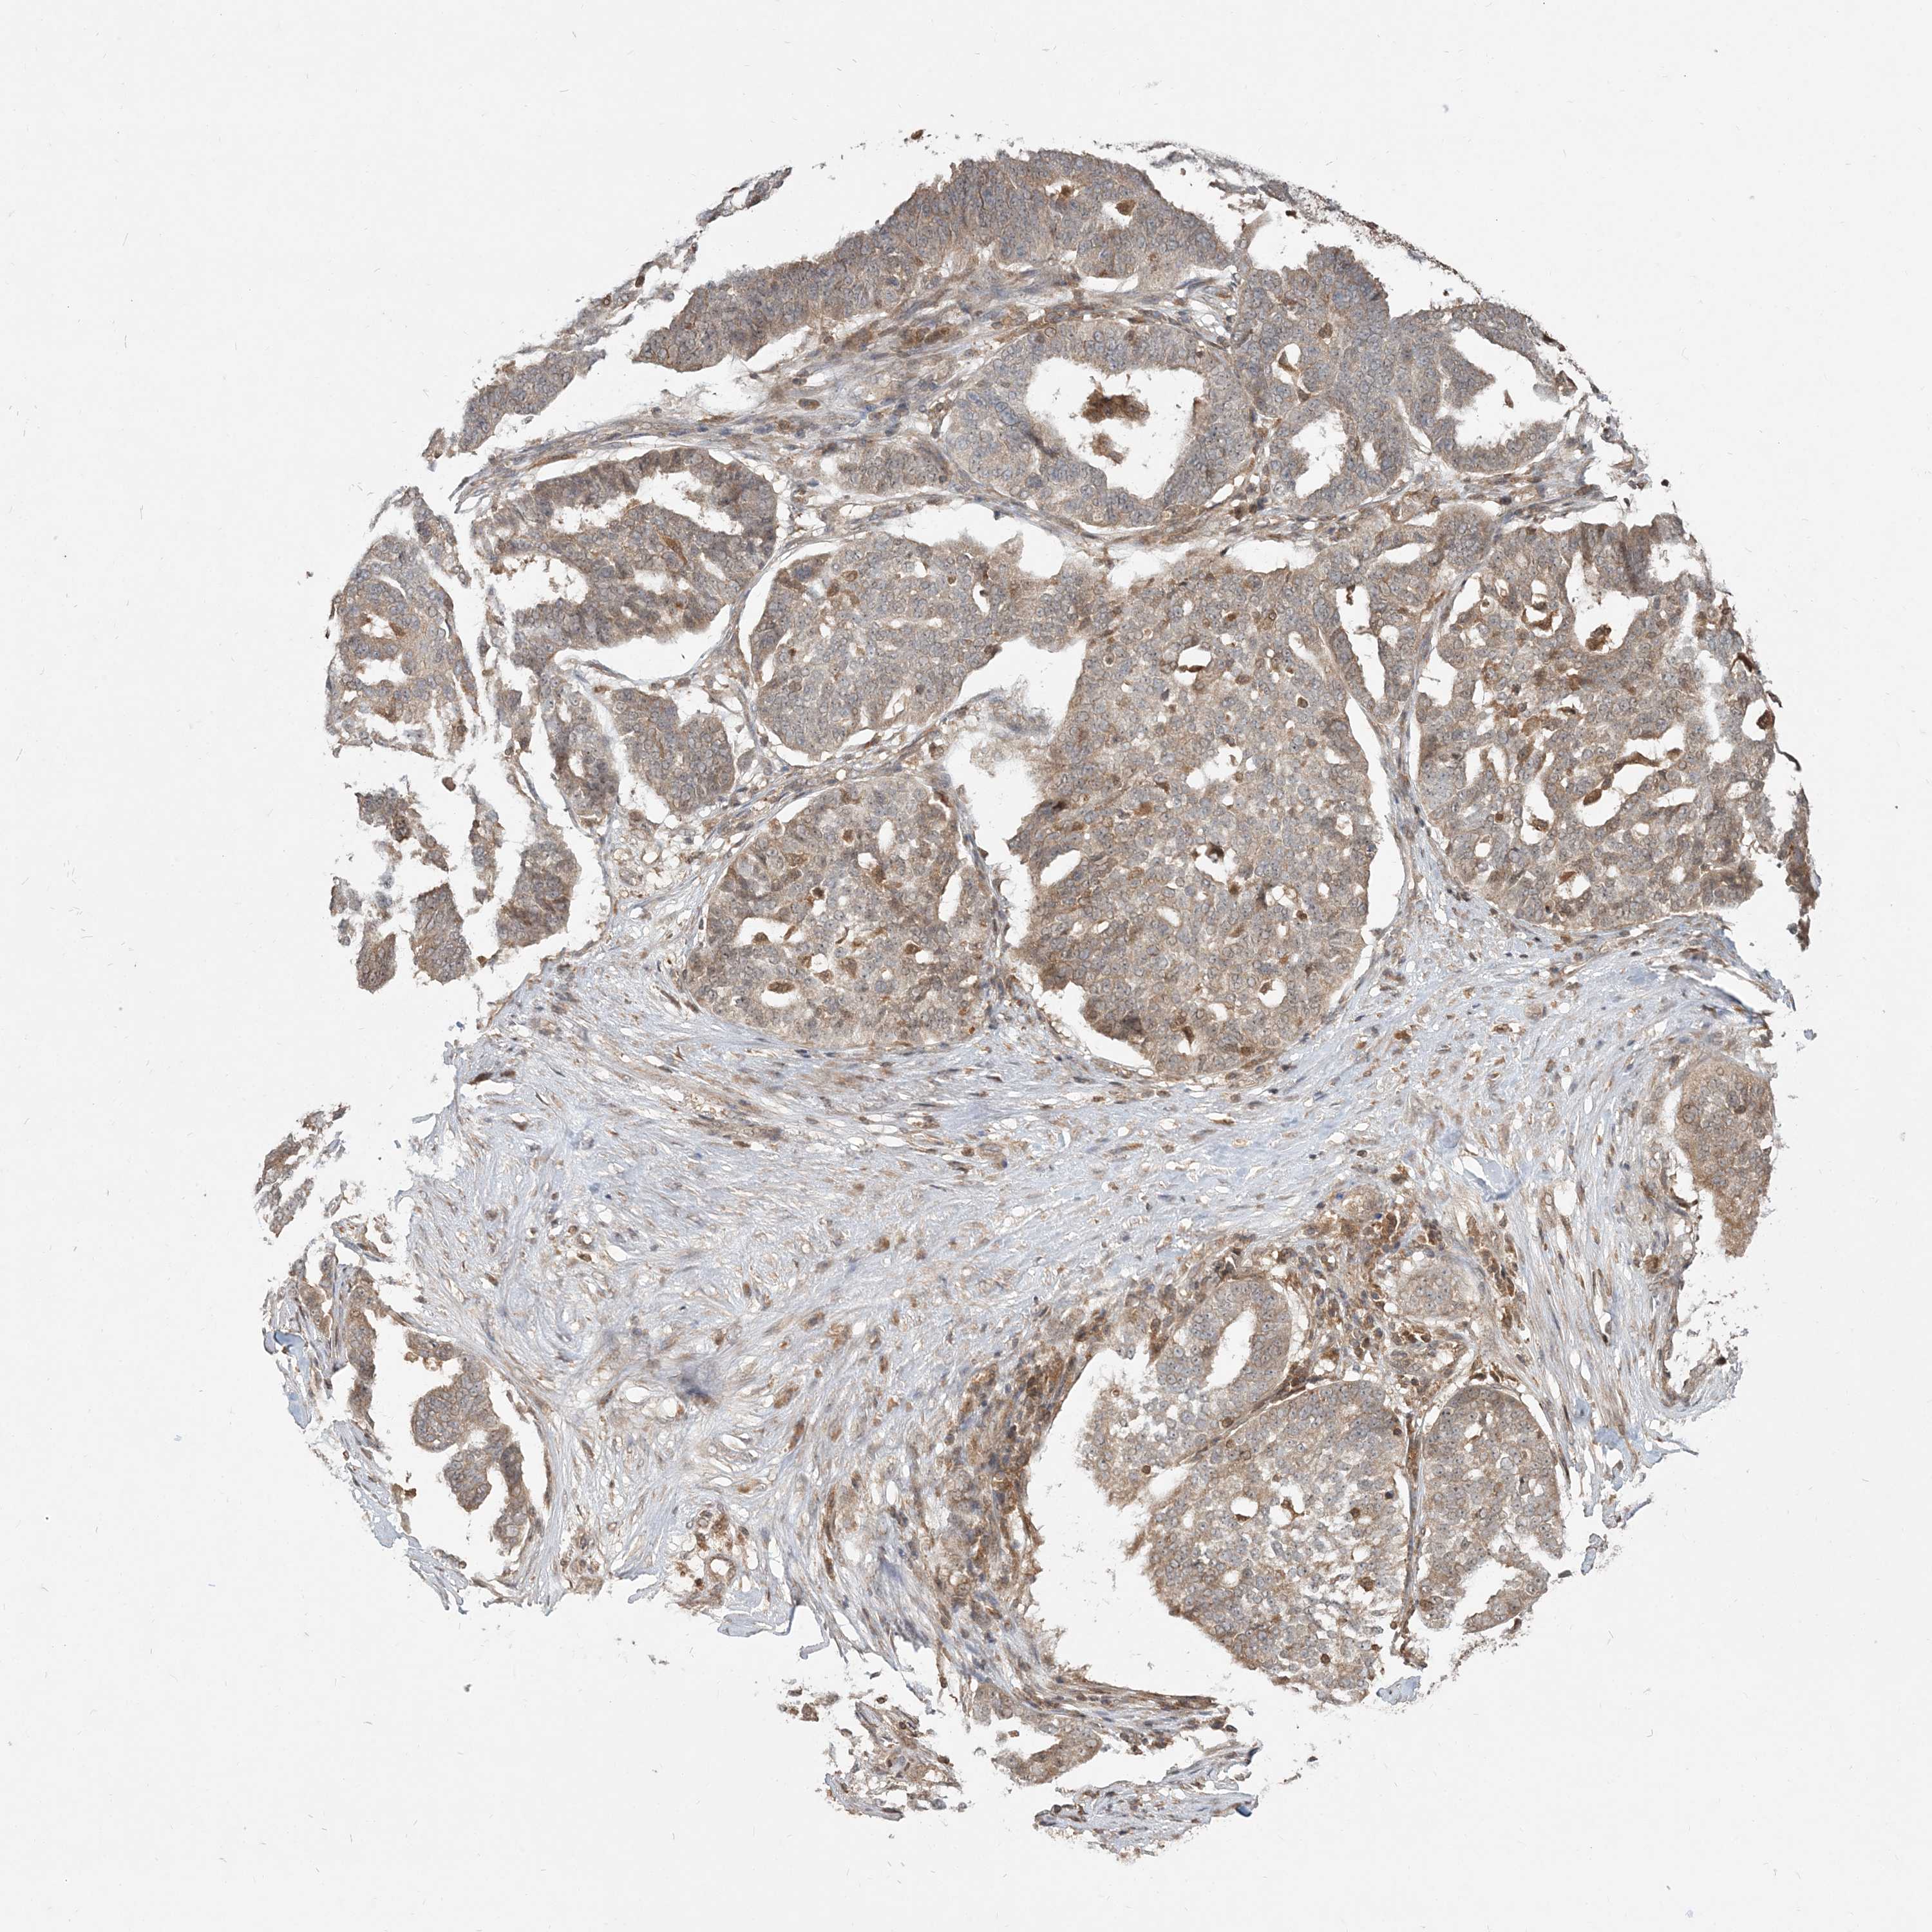

OVARIAN CANCER - Protein expressioni

A mouse-over function shows sample information and annotation data. Click on an image to view it in a full screen mode. Samples can be filtered based on level of antibody staining by selecting one or several of the following categories: high, medium, low and not detected. The assay and annotation is described here.

Note that samples used for immunohistochemistry by the Human Protein Atlas do not correspond to samples in the TCGA dataset.

Antibody stainingi

Antibody staining in the annotated cell types in the current human tissue is reported as not detected, low, medium, or high, based on conventional immunohistochemistry profiling in selected tissues. This score is based on the combination of the staining intensity and fraction of stained cells.

Each image is clickable and will lead to virtual microscopy that enables deeper exploration of all samples and also displays staining intensity scores, fraction scores and subcellular localization as well as patient and tissue information for each sample.

Antibody HPA076632

Antibody CAB037112

Cystadenocarcinoma, serous, NOS

Cystadenocarcinoma, mucinous, NOS

Carcinoma, endometroid

Carcinoma, NOS